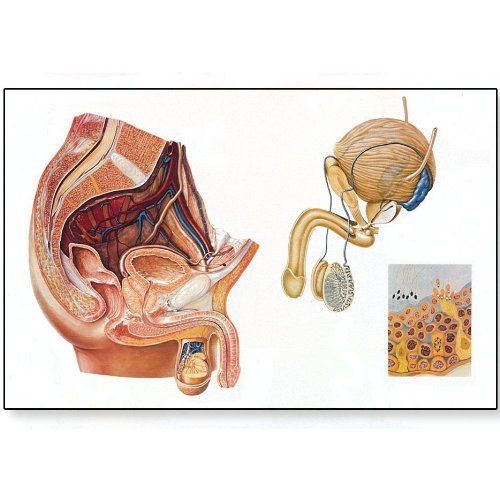

3B Scientific V2020M The Male Pelvic Organs Anatomical Chart with Wooden Rods